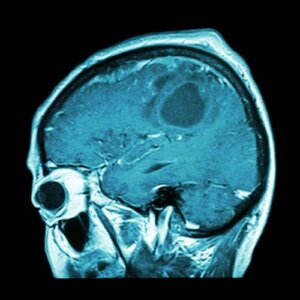

Szczepionka na raka mózgu wkrótce dostępna?

Rak mózgu jest jednym z najbardziej agresywnych. Jednak już opracowana szczepionka może być końcem tej choroby.